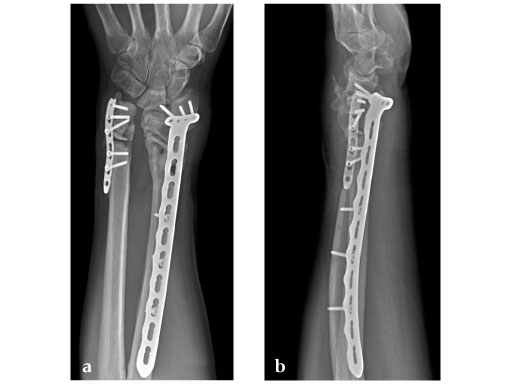

34-year-old male, with open fracture after motor vehicle accident.

Fig 1ab: Preoperative x-rays; primary stabilization with external fixator.

Fig 2ab: Eight months postoperative; full forearm rotation and 75% grip strength and wrist motion.